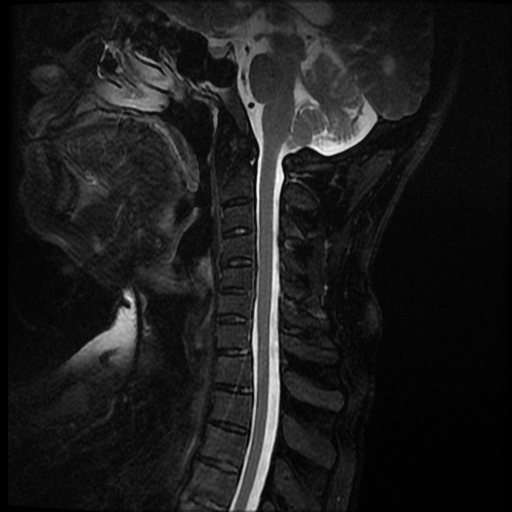

La espondilitis anquilosante (EA), es una enfermedad autoinmune inflamatoria crónica que afecta principalmente a las articulaciones de la columna vertebral y causa dolor crónico severo, afecta principalmente a las articulaciones de la columna, las articulaciones sacroilíacas y los tejidos blandos adyacentes, como los tendones y los ligamentos. En casos más avanzados, esta inflamación puede dar lugar a fibrosis y calcificación, dando como resultado la pérdida de flexibilidad y la fusión de la columna, asemejándose a un “bambú” con una posición inmóvil. Este caso se enfoca a paciente de 37 años de edad, que manifiesta rigidez y perdida de la linealidad de la columna cervical, encontrando a través del estudio de MRI calcificación de los ligamentos anterior y posterior de la columna cervical, más fusión de vértebras cervicales.

Ankylosing spondylitis (AS) is a chronic inflammatory autoimmune disease that primarily affects the joints of the spine and causes severe chronic pain. It primarily affects the joints of the spine, the sacroiliac joints, and adjacent soft tissues such as tendons. and the ligaments. In more advanced cases, this inflammation can lead to fibrosis and calcification, resulting in loss of flexibility and fusion of the spine, resembling a “bamboo” with an immobile position. This case focuses on a 37-year-old patient, who manifests rigidity and loss of linearity of the cervical spine, finding through the MRI study calcification of the anterior and posterior ligaments of the cervical spine, plus fusion of cervical vertebrae.

Se observa perdida de la lordosis normal de la columna cervical.

Se observa hipo intensidad del ligamento longitudinal anterior y posterior de la columna cervical, también se observa perdida de la movilidad y rigidez de la misma, los ligamentos interespinosos se ven hipointensos en T2 y en T1, al igual que el pliegue nucal, lo que sugiere calcificación de estas estructuras anatómicas.

Se observa fusión de las vertebras cervicales 5-6 y 6-7, dando la apariencia de bambú.

• Perdida de la lordosis

• Ligamentos espinales anterior, posterior, interespinosos y pliegue nucal calcificados

• Fusión de vertebras cervicales 5-6 y 6-7.